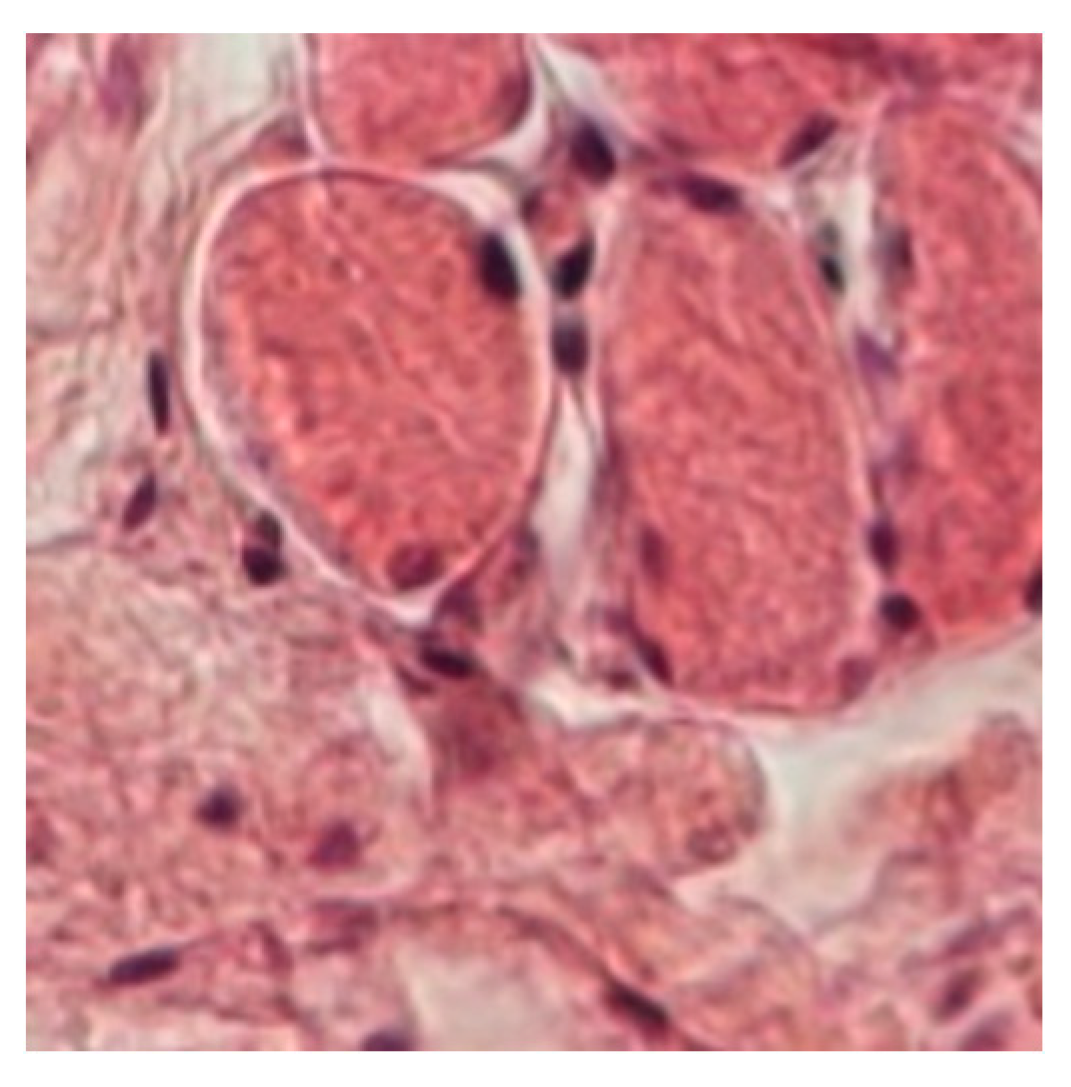

3.2.2. Muscle

3.3. Number of Angiogenesis Vessels/Microscopic field

3.3.2. Muscle